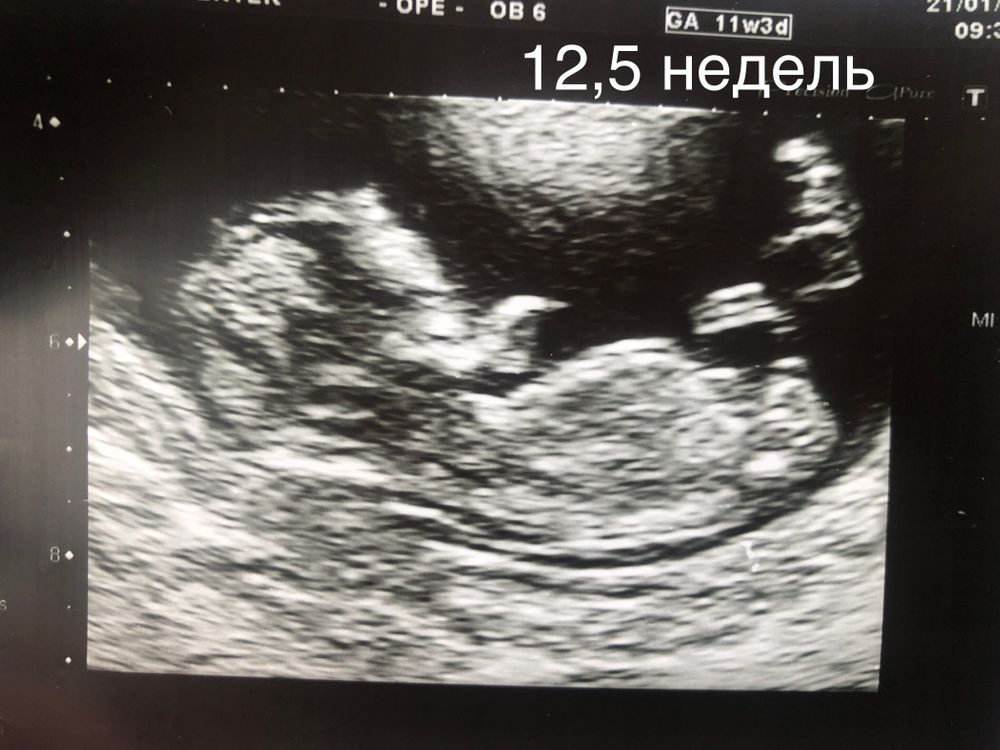

Первый скрининг и пол малыша

Если на снимке половой бугорок, то он параллельно телу. Визуализация плохая с этого ракурса. Но думаю, что девочка.

Закрылся малыш

Не видно, ножкой закрывает, видно только бедро

Юля С, вот и я только ножку вижу